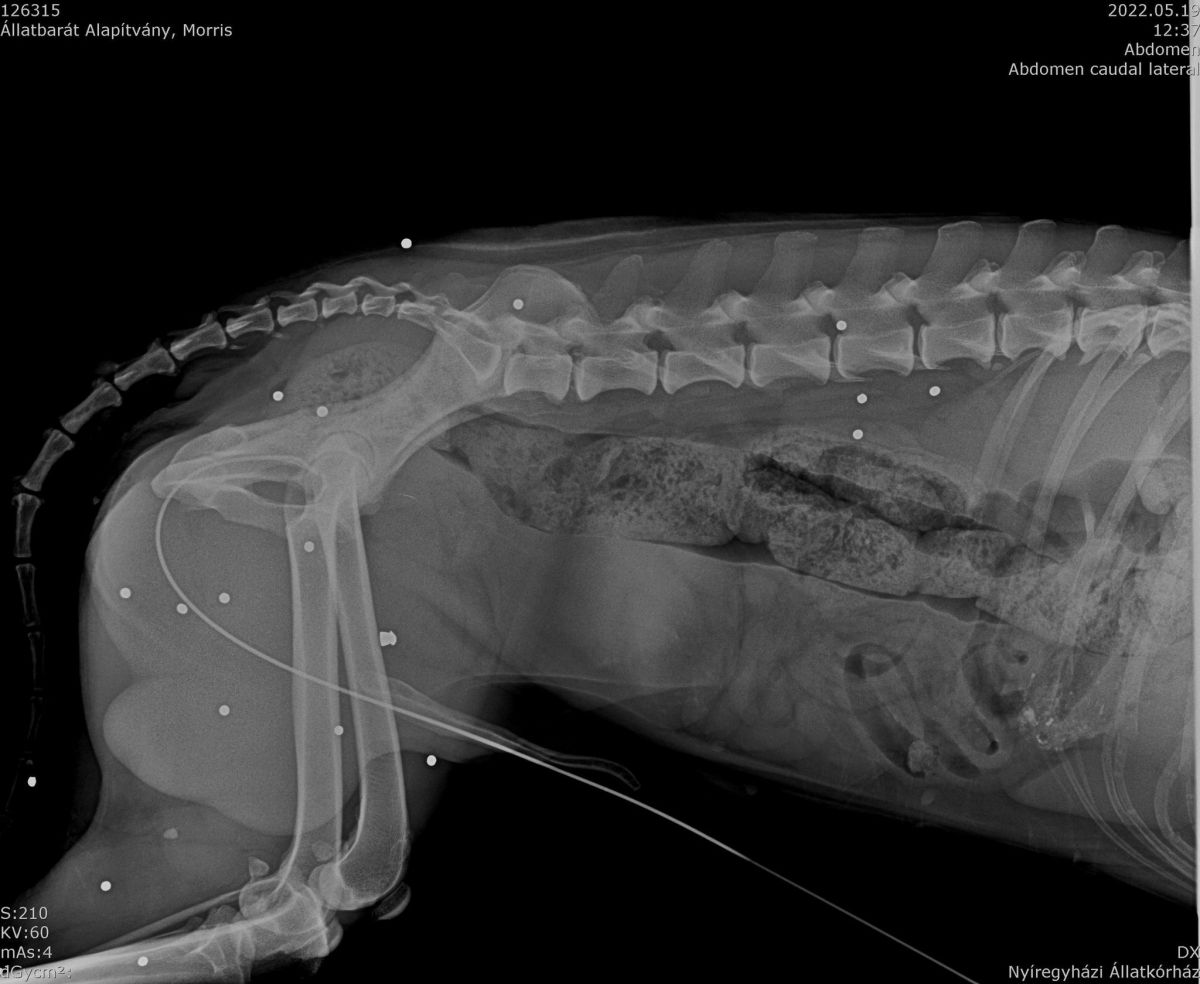

Zudem wurde durch Abtasten festgestellt, dass seine Blase übermäßig gefüllt war. Ausdrücken war nicht möglich und den Katheter einführen auch nicht. Ein dünnerer wurde versucht einzuführen. Dieses klappte mit hängen und würgen. Dann wurden direkt Röntgenbilder gemacht. Und siehe da, auf Morris wurde geschossen. Und vermutlich blockiert eine Kugel, oder Schrot, den Harnweg. Was der arme Kerl ertragen muss, nicht vorzustellen.... Dieses Problem wird nun in Angriff genommen,